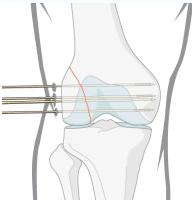

Cannulated Screws:

- Hollow to be inserted over a wire

- Makes insertion more accurate in minimally invasive techniques